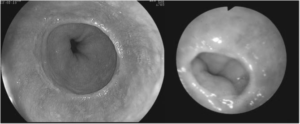

Эндоскопические исследование позволяет визуализировать кольца Шацкого

- Эндоскопическое обследование(фиброэзофагогастроскопия) является «золотым» стандартом в выявлении колец Шацкого. Данный метод позволяет врачу визуально оценить состояние стенки пищевода, а так же выявить локализацию и степень сужения его просвета. Метод абсолютно безвреден для больного и может вызвать только незначительный дискомфорт.

Эндоскоп вводят через ротовую полость, с последующим выведением видеосъемки пищевода на экран монитора. Это позволяет визуализировать патологию с высокой точностью изображения.

Диагностика пищевода с помощью гастроскопии

Но этот метод имеет существенный недостаток. Эндоскопическая трубка может проходить по суженному просвету пищевода со значительным трудом. При наличии в пищеводе очень большого кольца Шацкого трубка эндоскопа может вообще не пройти.